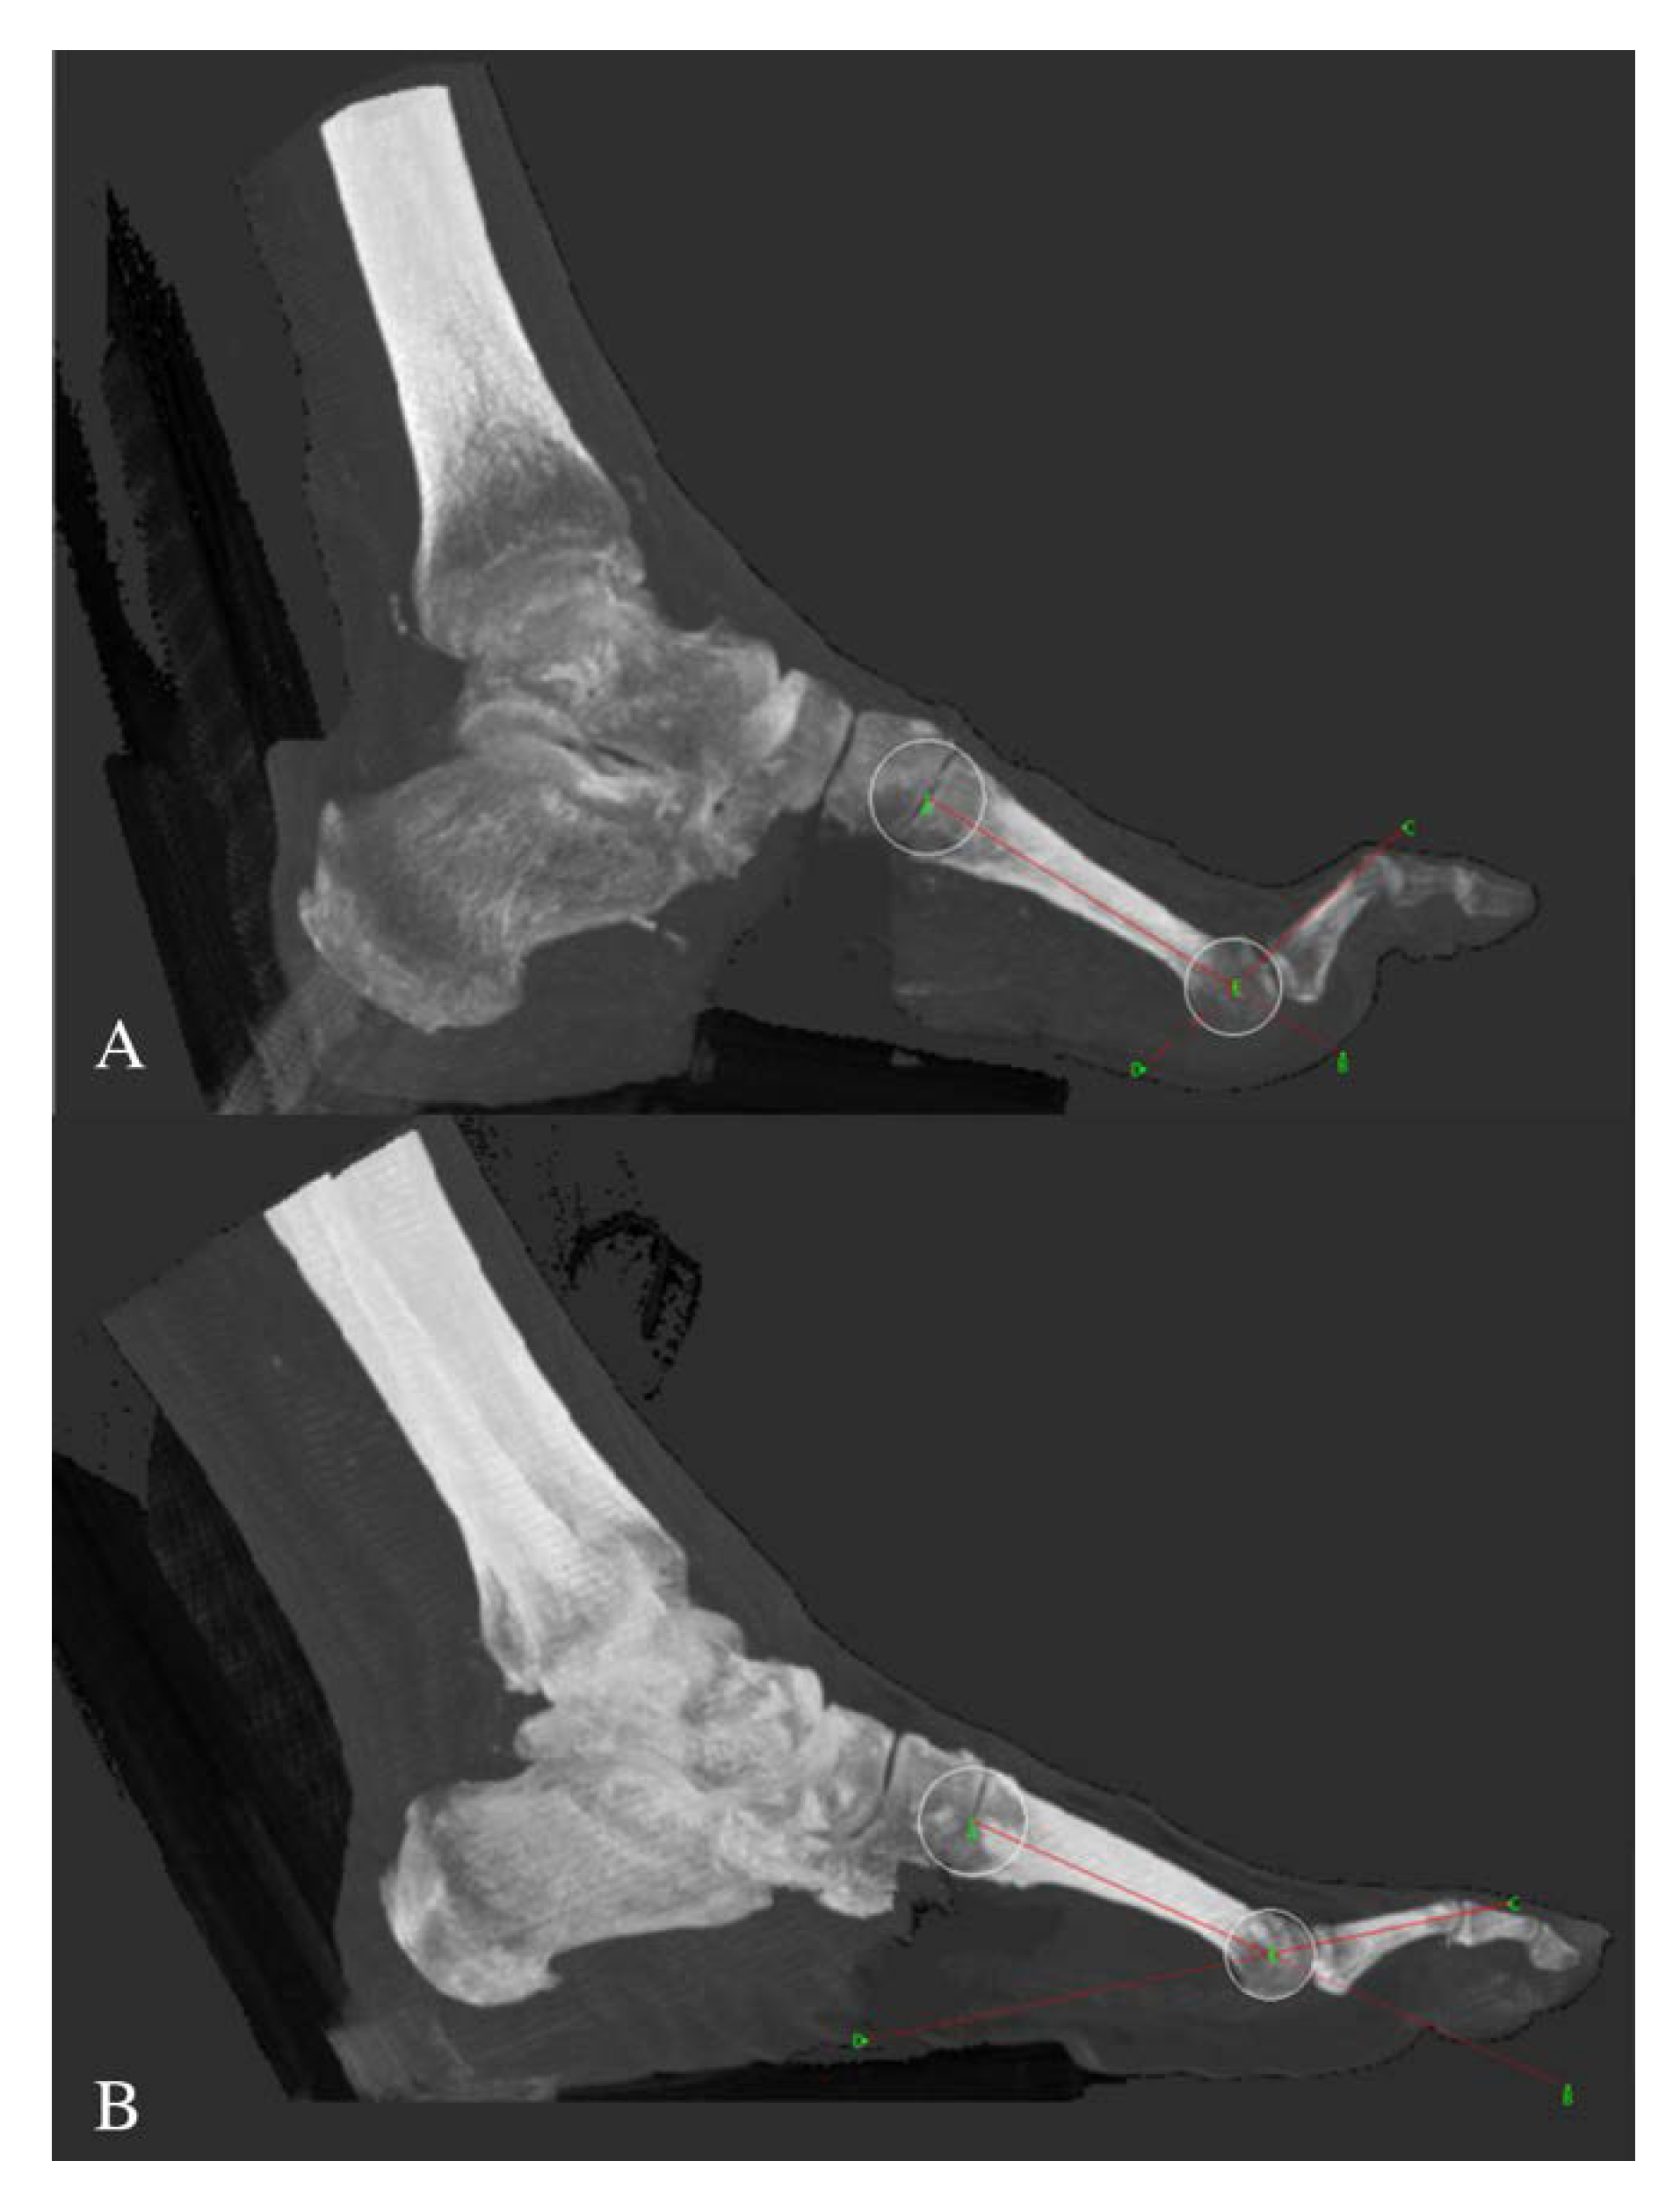

2.2. MTP Joint Deformity Assessment

- Smith, K.E.; Commean, P.K.; Robertson, D.D.; Pilgram, T.; Mueller, M.J. Precision and accuracy of computed tomography foot measurements. Arch. Phys. Med. Rehabil. 2001, 82, 925–929. [Google Scholar] [CrossRef] [PubMed]

- Hastings, M.K.; Woodburn, J.; Mueller, M.J.; Strube, M.J.; Johnson, J.E.; Beckert, K.S.; Stein, M.L.; Sinacore, D.R. Radiographic-directed local coordinate systems critical in kinematic analysis of walking in diabetes-related medial column foot deformity. Gait Posture 2014, 40, 128–133. [Google Scholar] [CrossRef]